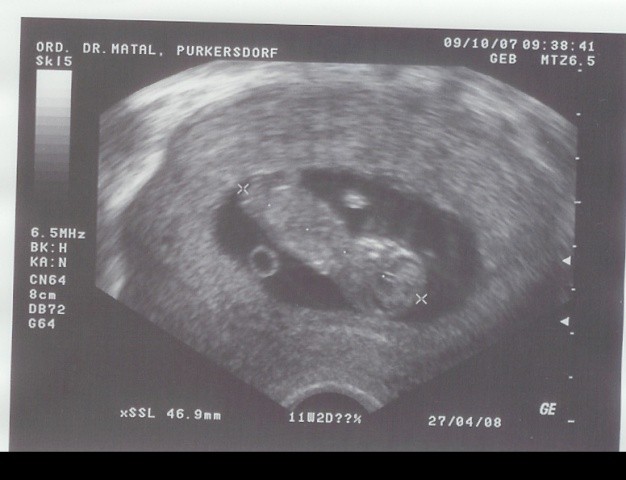

Znalazłam jeszcze fajne fotki :-) Teraz oczywiście nie jestem już tak "szczupła"![]()